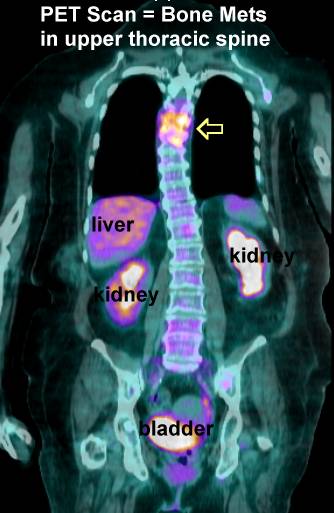

PET Scans of Bone Metastases

PET scans may show these lesions best (go here , here, here, here, here, here, here , here , here , here , here , here , here and here) even better than CT scans (go here , here, here and here) and better than MRI (here). PET scans also show the response to radiation (go here). PET is helpful for hard to see areas like the ribs or scapula. PET's may be best for

osteolytic lesions and bone scans best for blastic metastases (go

here). |